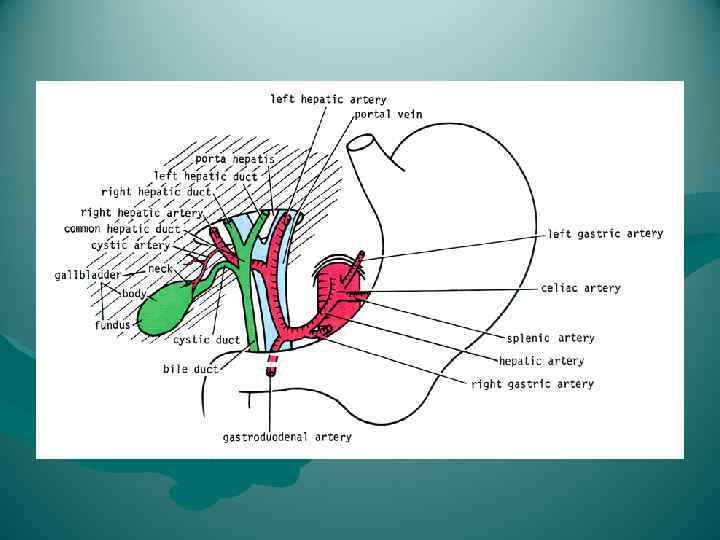

Lig. Hepatoduodenale Cлева печеночная артерия и ее ветви, справа — общий желчный проток и формирующие его общий печеночный и пузырный протоки, между ними и сзади — воротная вена, v. portae. В самом нижнем отделе связки проходят правые желудочные, a. et v. gastricae dextrae, и желудочно-двенадцатиперстные, a. et v. gastroduodenales, сосуды.

Lig. Hepatoduodenale Cлева печеночная артерия и ее ветви, справа — общий желчный проток и формирующие его общий печеночный и пузырный протоки, между ними и сзади — воротная вена, v. portae. В самом нижнем отделе связки проходят правые желудочные, a. et v. gastricae dextrae, и желудочно-двенадцатиперстные, a. et v. gastroduodenales, сосуды.

а) Типичное кровоснабжение; б) правая печеночная артерия, исходящая из верхней брыжеечной артерии, в) добавочная левая печеночная артерия, исходящая из левой желудочной артерии; г) сразу же после отхождения от чревного ствола общая печеночная артерия делится на правую и левую ветви, которые проходят друг возле друга, достигая печени через печеночно-двенадцатиперстную связку; д) правая печеночная артерия пересекает общий печеночный проток не сзади, а спереди; е) две пузырных артерии исходят от правой печеночной артерии; ж) пузырная артерия отходит от общей печеночной артерии и пересекает желчный проток не сзади, а спереди; з) пузырная артерия исходит из левой печеночной артерии и пересекает желчный проток спереди; и) имеются две пузырных артерии: одна отходит, как правило, от правой печеночной артерии и достигает желчного пузыря, пересекая общий желчный проток, как и в норме, сзади, тогда как другая пузырная артерия чаще всего отходит от общего ствола печеночной артерии (или от одного из ее стволов) и пересекает общий желчный проток спереди; к) пузырная артерия отходит от левой стороны правой печеночной артерии, при этом оба сосуда образуют петлю; если пузырную артерию перевязать в глубине, то в этом случае в лигатуру может легко попасть и правая печеночная артерия

а) Типичное кровоснабжение; б) правая печеночная артерия, исходящая из верхней брыжеечной артерии, в) добавочная левая печеночная артерия, исходящая из левой желудочной артерии; г) сразу же после отхождения от чревного ствола общая печеночная артерия делится на правую и левую ветви, которые проходят друг возле друга, достигая печени через печеночно-двенадцатиперстную связку; д) правая печеночная артерия пересекает общий печеночный проток не сзади, а спереди; е) две пузырных артерии исходят от правой печеночной артерии; ж) пузырная артерия отходит от общей печеночной артерии и пересекает желчный проток не сзади, а спереди; з) пузырная артерия исходит из левой печеночной артерии и пересекает желчный проток спереди; и) имеются две пузырных артерии: одна отходит, как правило, от правой печеночной артерии и достигает желчного пузыря, пересекая общий желчный проток, как и в норме, сзади, тогда как другая пузырная артерия чаще всего отходит от общего ствола печеночной артерии (или от одного из ее стволов) и пересекает общий желчный проток спереди; к) пузырная артерия отходит от левой стороны правой печеночной артерии, при этом оба сосуда образуют петлю; если пузырную артерию перевязать в глубине, то в этом случае в лигатуру может легко попасть и правая печеночная артерия